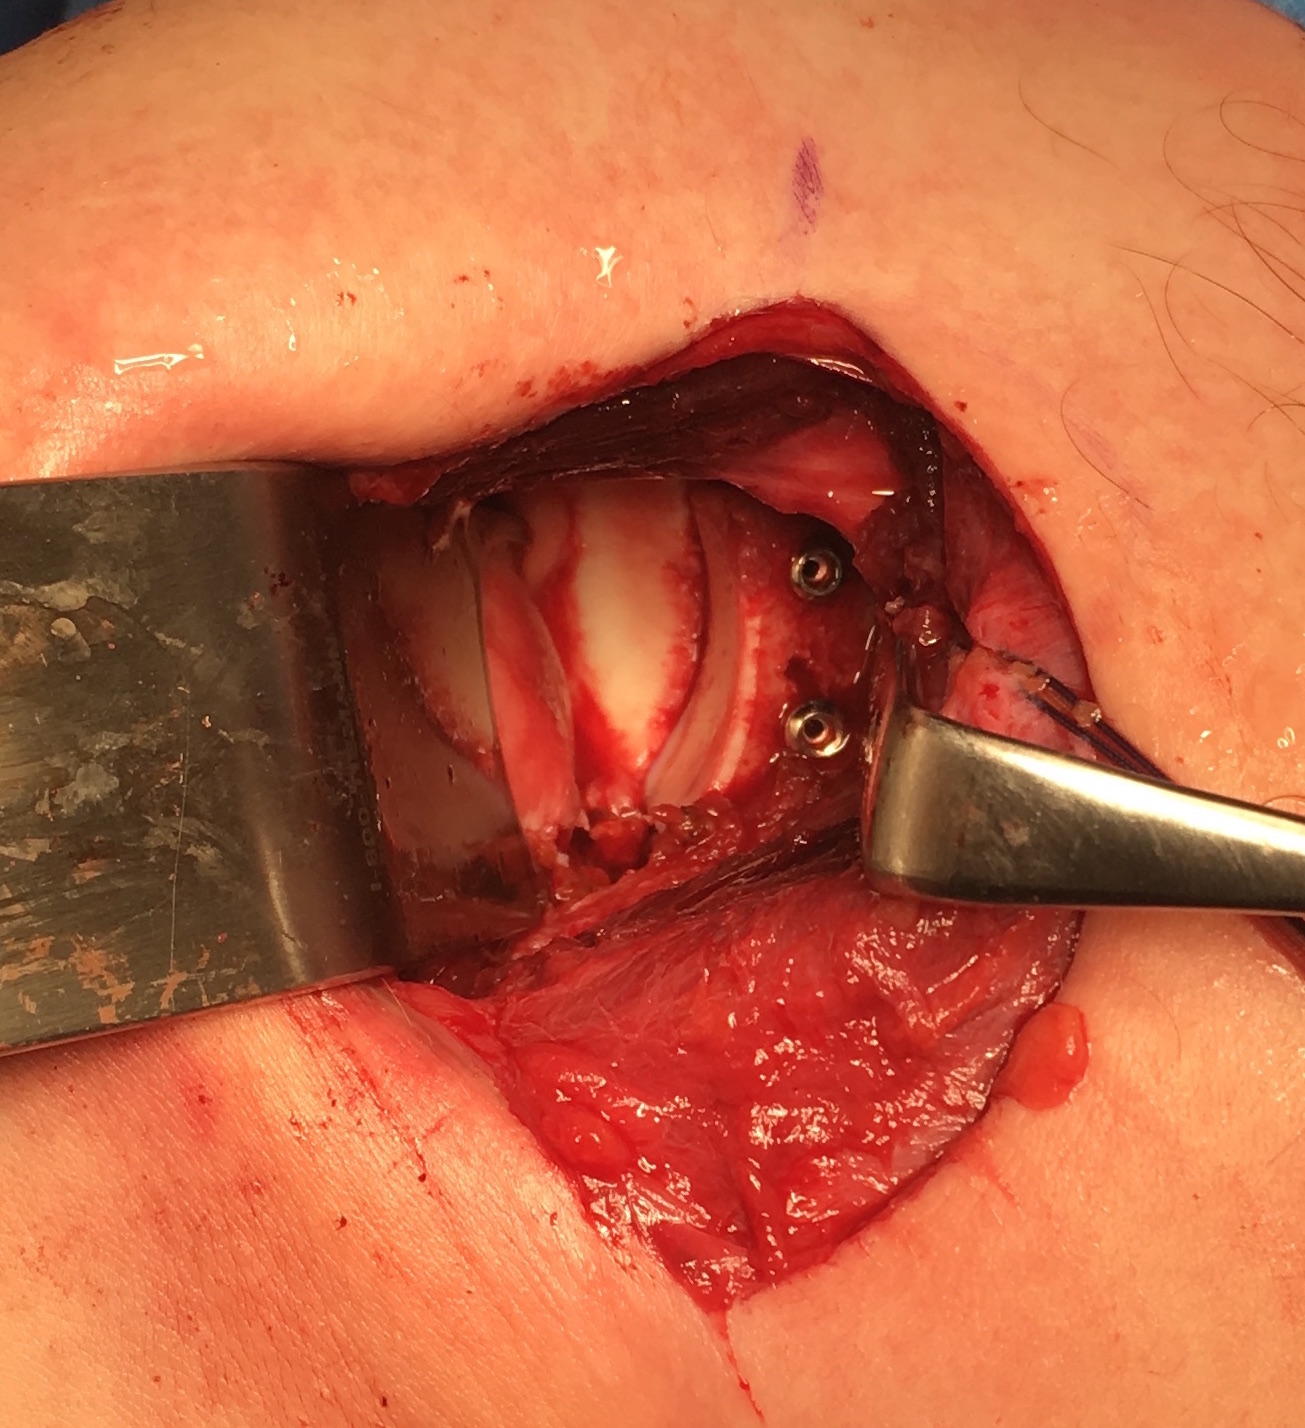

Case 1: Failed Latarjet

![]()